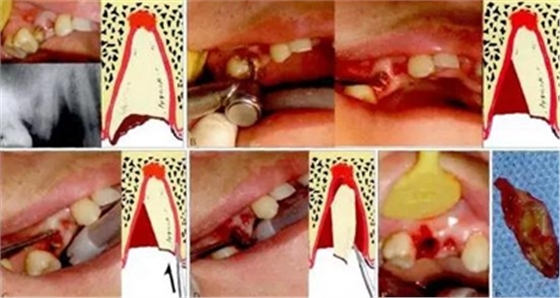

3.3.2 轉(zhuǎn)動(dòng)軸、轉(zhuǎn)動(dòng)半徑與差動(dòng)

對(duì)于粗大、彎曲的牙根,要消除脫位的阻力,可以通過設(shè)計(jì)轉(zhuǎn)動(dòng)軸心,使得牙根在運(yùn)動(dòng)過程中,能順著彎曲的牙槽窩而脫位,這涉及轉(zhuǎn)動(dòng)半徑與差動(dòng)的原理,即在一個(gè)剛性物體上某一點(diǎn)施加同樣的力量,由于轉(zhuǎn)動(dòng)軸心的變化,這一剛體其他點(diǎn)的運(yùn)動(dòng)

方向?qū)l(fā)生變化。牙根脫位過程中,運(yùn)動(dòng)支點(diǎn)也就是運(yùn)動(dòng)軸心點(diǎn)的位置變化,直接導(dǎo)致牙根受力時(shí),轉(zhuǎn)動(dòng)半徑的變化,并進(jìn)一步影響牙根根尖部位的運(yùn)動(dòng)方向和角動(dòng)量,從而使其易于脫位(圖5、6)。

圖5 轉(zhuǎn)動(dòng)與差動(dòng)。A:口內(nèi)(左上)和X線片(左下)見15殘根,需拔除,右圖為示意圖;B:通過渦輪鉆切割(左),挺除遠(yuǎn)中部分牙根(中)后,形成遠(yuǎn)中(凹面)低點(diǎn)的斷面(右);C:在近中插入分離器械;D:牙根轉(zhuǎn)動(dòng)脫位;E:達(dá)成微創(chuàng)拔除

的效果;F:拔除的牙根可見切割形成的斷面。

圖6 剖根的深度和差動(dòng)。同樣的牙根,剖根深度不同,根尖部位的運(yùn)動(dòng)方向?qū)l(fā)生顯著變化,從而導(dǎo)致牙齒脫位的阻力不同。左圖中牙根脫位時(shí),插入牙挺時(shí),用力方向如藍(lán)色箭頭所示,牙根的運(yùn)動(dòng)軸心點(diǎn)是O,阻力點(diǎn)位置的運(yùn)動(dòng)方向(綠色箭頭方

向)受骨壁阻擋。而右圖中牙根被進(jìn)一步切割,運(yùn)動(dòng)軸心點(diǎn)(O)進(jìn)一步下降,同樣的阻力點(diǎn)的運(yùn)動(dòng)方向就變成了向上,避開了骨壁的剛性阻擋而得以脫位